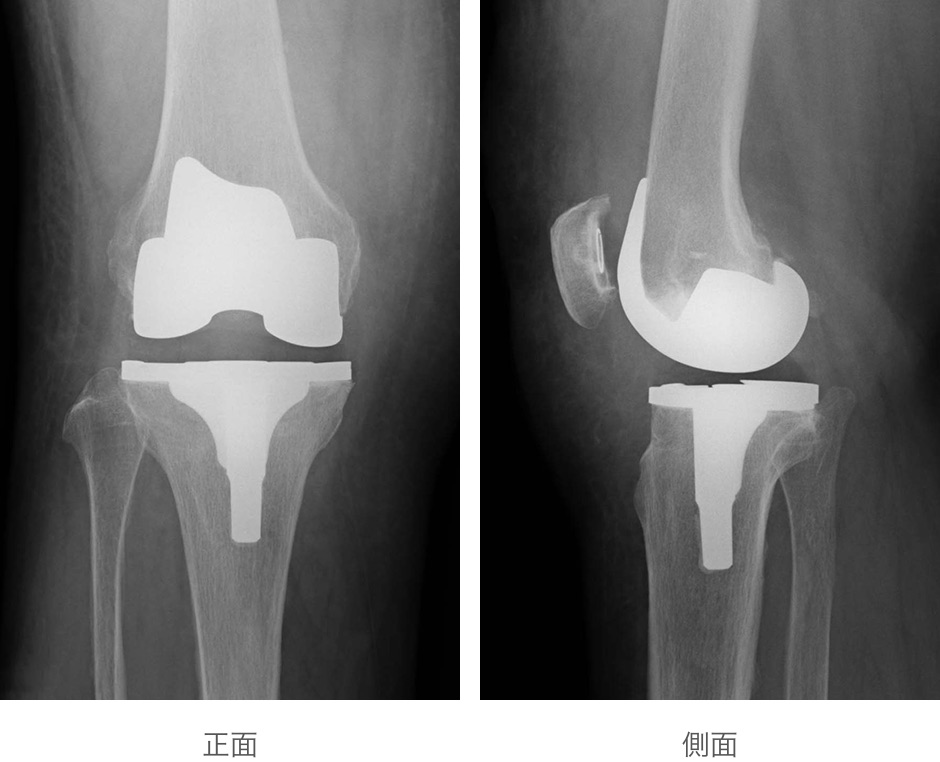

手術中、外科医は損傷した軟骨と骨を除去した後、金属、プラスチック、その他の合成材料で構成される人工関節を移植します。

米国整形外科医学会(AAOS)によると、膝関節全置換術を受けた人の90%以上は、術後の痛みが大幅に軽減され、動き回ったり日常生活を行う能力が向上したとのことです。